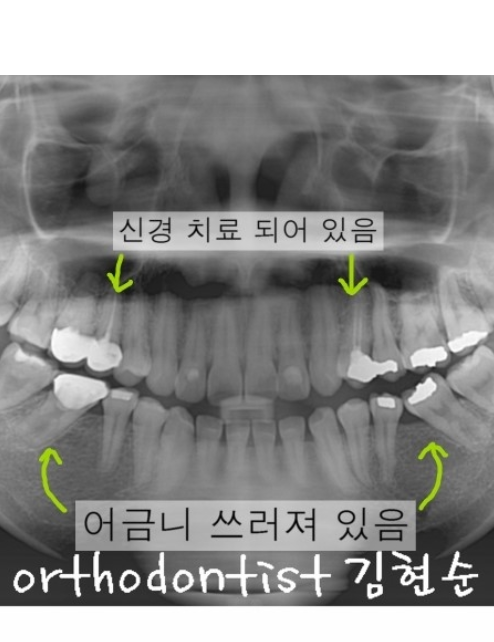

그런데 이번 케이스는

돌출입 말고도 또 다른 문제가 있었습니다.

다름 아닌 충치 때문에 빠진 어금니 자리에

공간이 생기면서 뒤에 있는 어금니가

앞으로 심하게 누워 있는 어려운 상황!!

앞으로 쓰러진 어금니를

바로 세우고 난

빈 공간을 이용해서

앞니를 뒤로 당겨

돌출입까지 해결했습니다.